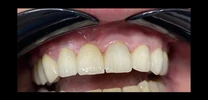

Zirconium Applications

Porcelain Applications

Laminate Veneer